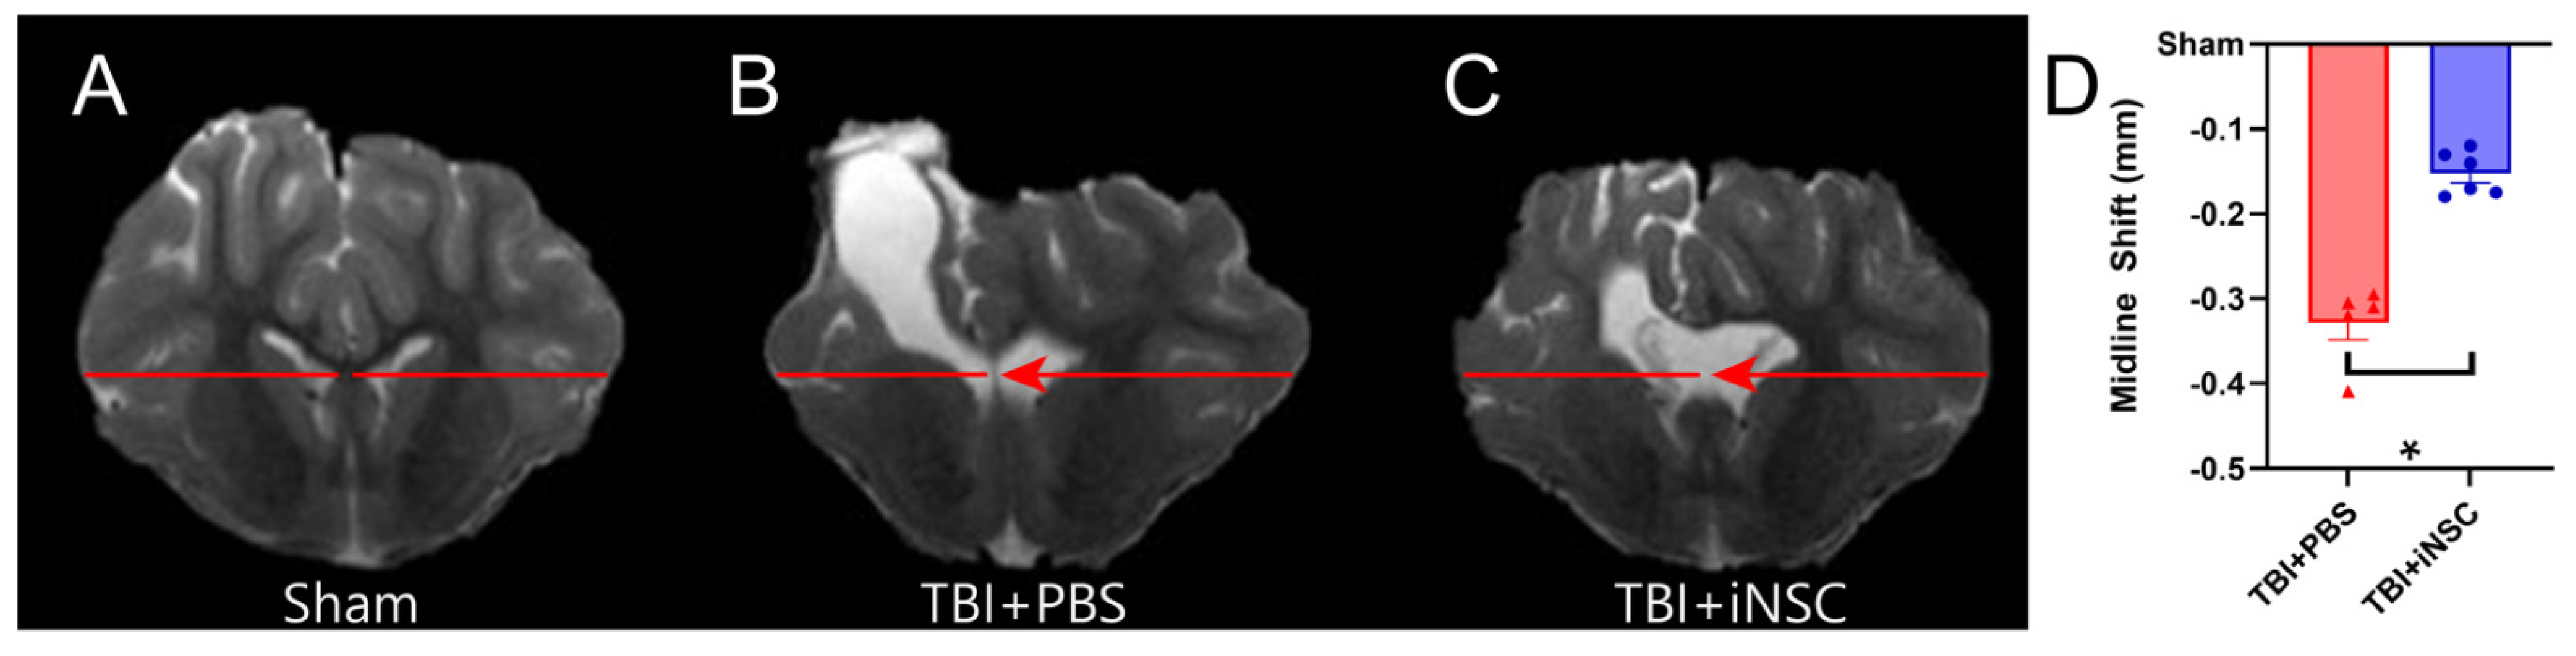

3.4. iNSC Transplantation Significantly Decreased Ipsilateral Atrophy, Lesion Volume, and Midline Shift While Preserving Cerebral Blood Flow

- Puffer, R.C.; Yue, J.K.; Mesley, M.; Billigen, J.B.; Sharpless, J.; Fetzick, A.L.; Puccio, A.; Diaz-Arrastia, R.; Okonkwo, D.O. Long-term outcome in traumatic brain injury patients with midline shift: A secondary analysis of the Phase 3 COBRIT clinical trial. J. Neurosurg. 2018, 131, 596–603. [Google Scholar] [CrossRef] [PubMed]